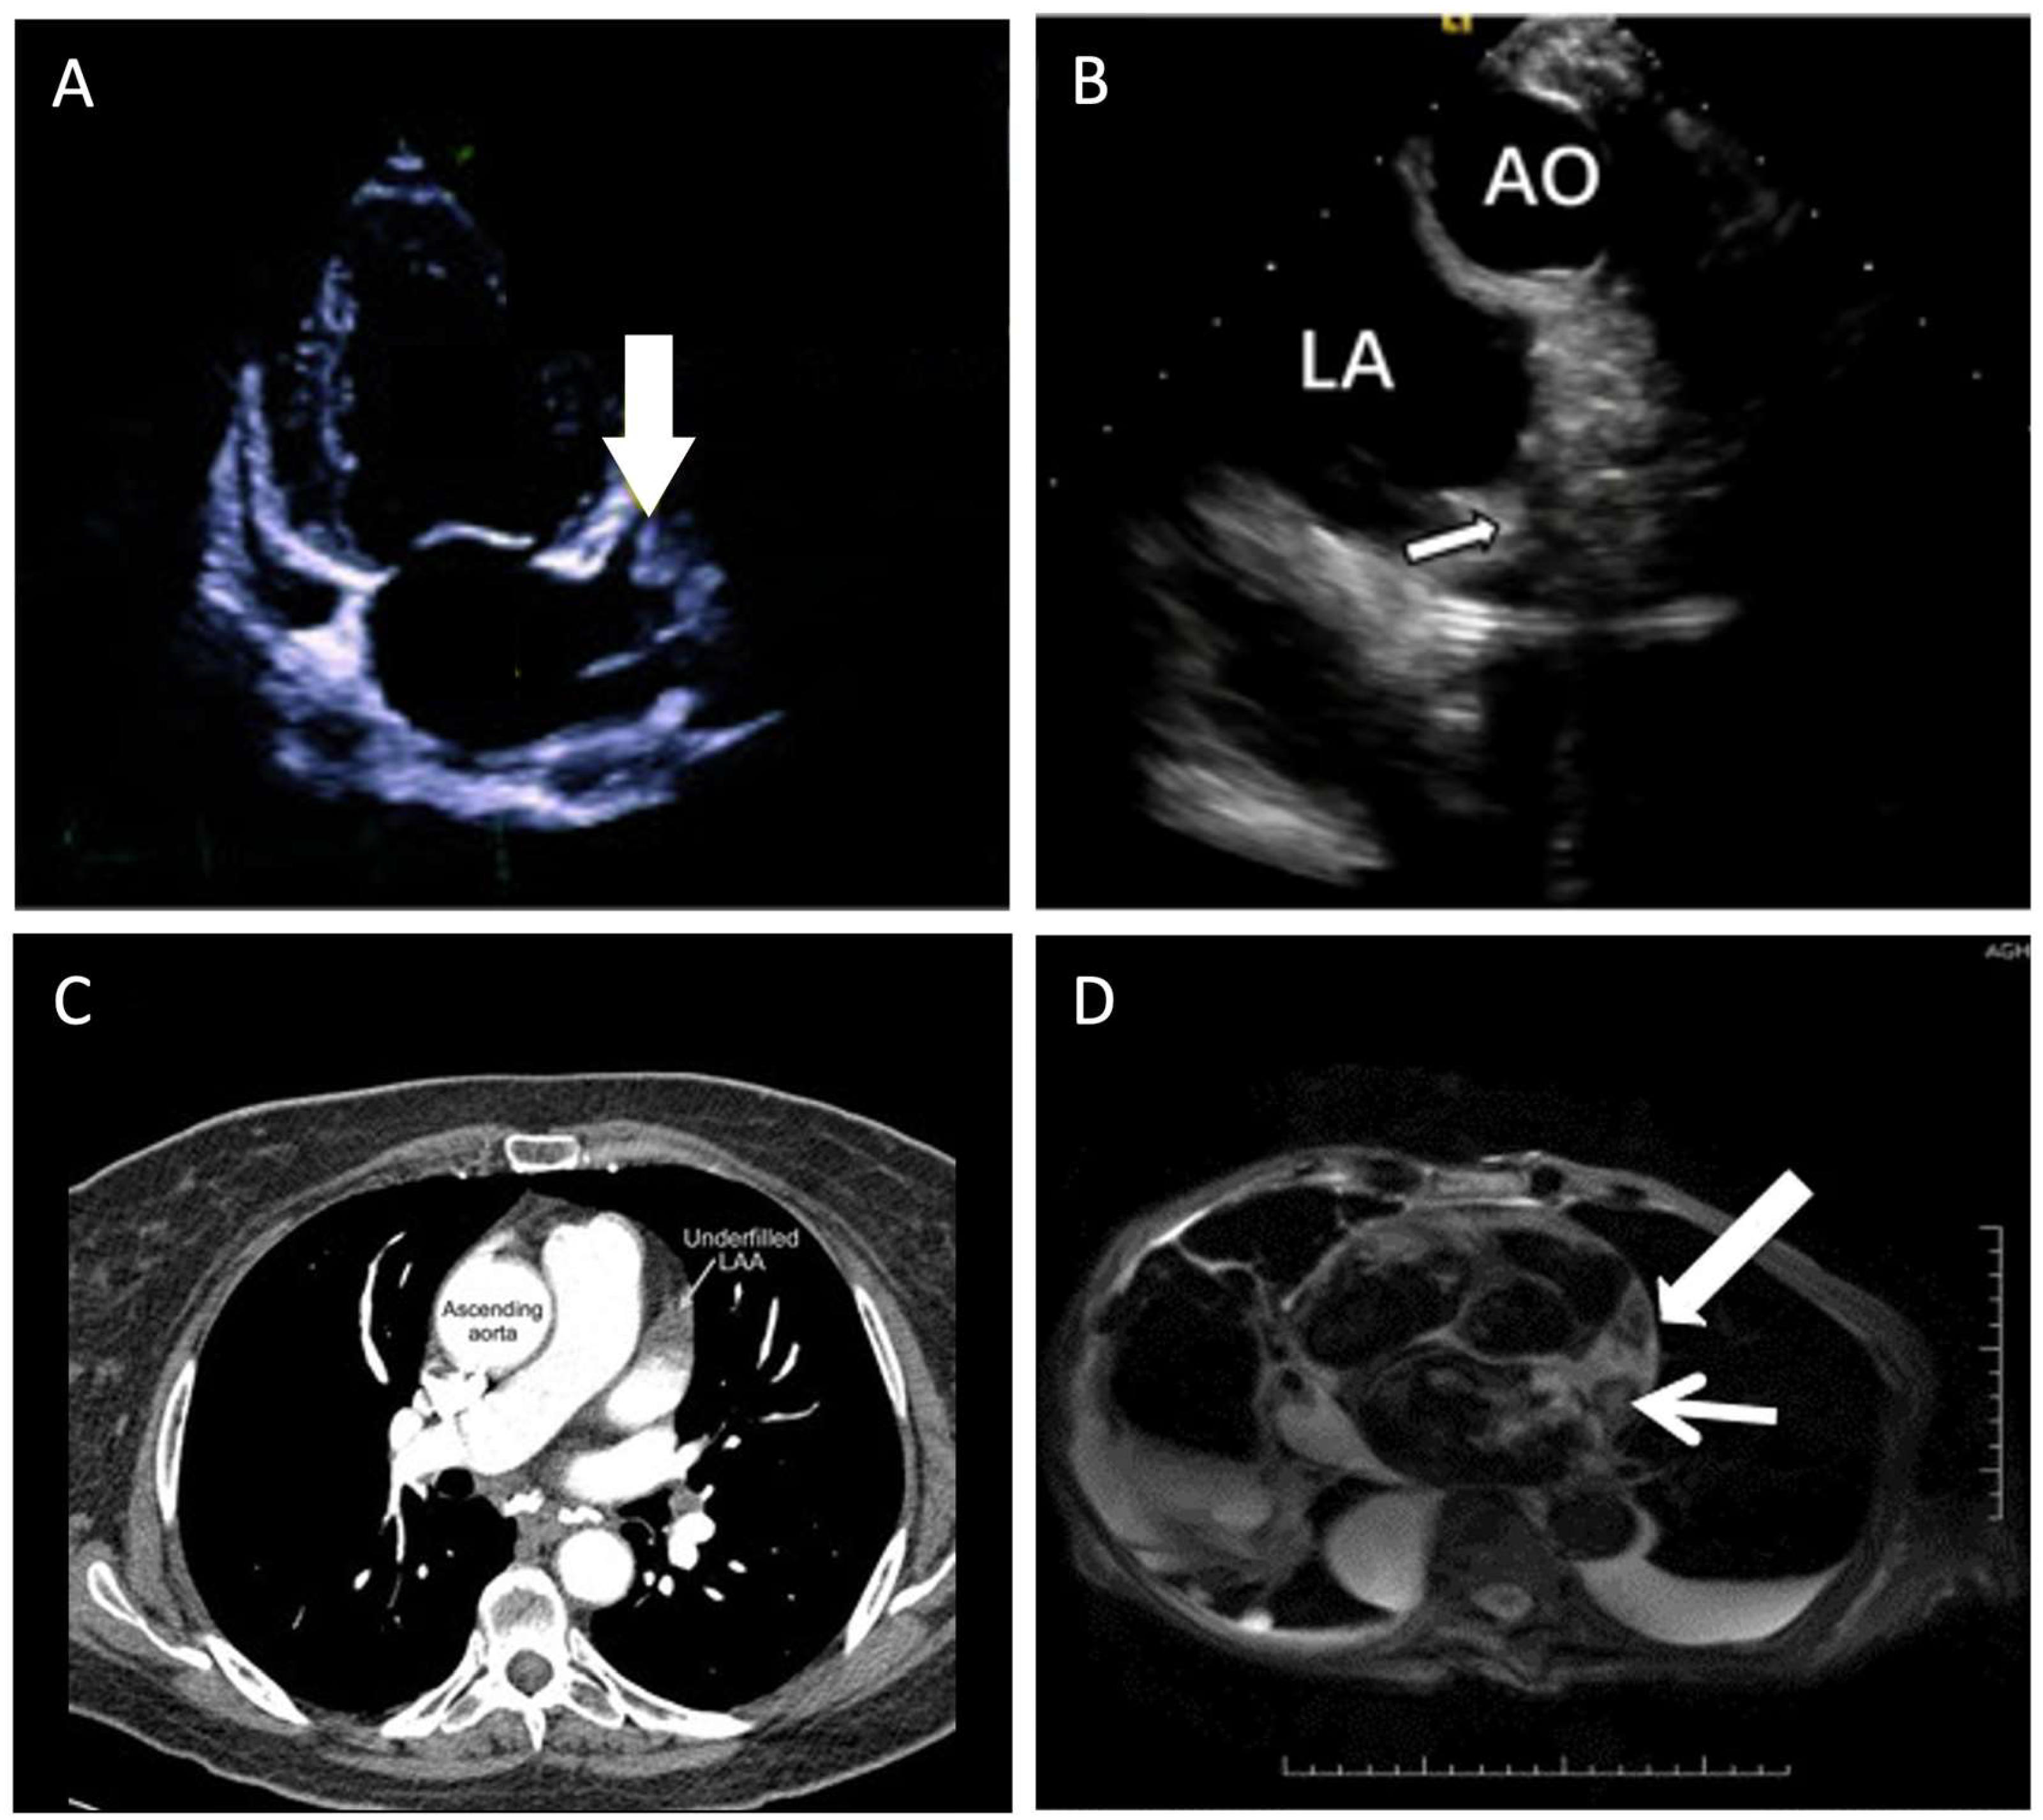

Currently, the modality of choice for evaluating LAA is transesophageal echocardiography (TEE). Other non-invasive imaging modalities such as cardiac magnetic resonance (CMR), multi-detector computed tomography (MDCT), and intracardiac echocardiography (ICE) can also be used. The different imaging modalities can be found in Figure 1.

Figure 1.

Imaging modalities to evaluate the left atrial appendage. (A) Transesophageal echocardiography—apical two chamber view during transthoracic echocardiogram without contrast showing thrombus in LAA [25]. (B) Intracardiac echocardiography—view from right ventricular outflow tract [26]. (C) Multi-detector computed tomography—axial image using MDCT showing underfilled or “abnormal” LAA with failure of contrast to fill the LAA (arrow) [27]. (D) Cardiac magnetic resonance—CMR paraxial view demonstrating T2-weighted image of the LA and LAA with fresh clot (narrow arrow) showing higher signal intensity than the old clot with reduced central signal intensity (broad arrow) [28]. AO—aorta, LA—left atrium, LAA—left atrial appendage, MDCT—multi-detector computed tomography, CMR—cardiac magnetic resonance.